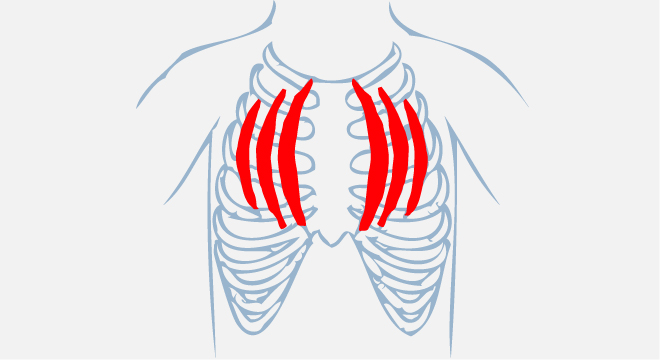

Das Rippenfell (Pleura pulmonalis) bewirkt, dass die Lungenflügel eng am Brustkorb anliegen. Die Lunge kann sich aber bei den Atembewegungen trotzdem leicht verschieben. Das Brustfell  (Pleura parietalis) bedeckt die Innenwände des Brustkorbs, die Oberseite des Zwerchfells und den Herzbeutel. Bei der normalen Atmung liegen beide Schichten (das Rippen- und das Brustfell) aufeinander; dazwischen befindet sich ein feiner Flüssigkeitsfilm.

• Schneidende Schmerzen in der Brust, beim Einatmen und Husten verstärkt

• Flache Atmung

• Reizhusten (kein Auswurf)